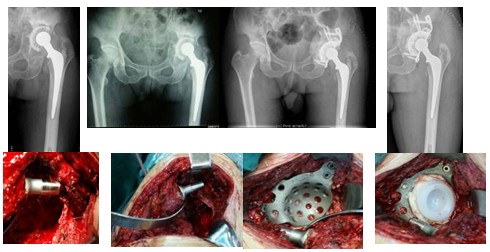

2、髋臼骨缺损重建的方法与假体选择

骨缺损重建常与假体选择相结合,更具骨缺损的范围和分类不同,常用的方法有:(1)植骨+非骨水泥臼;(2)打压植骨+Cage/Ring+骨水泥臼;(3)结构植骨+颗粒植骨+Cage+骨水泥臼。

如果骨缺损较大,应考虑采用髋臼加强环,在加强环内植入骨水泥型髋臼假体。髋臼加强环的作用为:①扩大与髋臼骨床接触,加强固定;②应力旁路传导作用,保护移植骨过度承载;③为骨水泥安放提供稳定的平台。

1.打压植骨+ Cage+ 骨水泥臼杯

(4)、IV型骨缺损

结构植骨+颗粒植骨+Cage+骨水泥臼